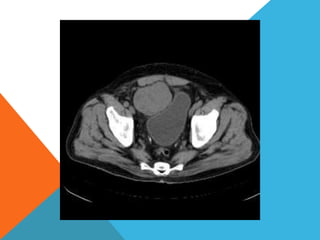

El paciente presentó síntomas de sangrado digestivo y pérdida de peso. Exámenes revelaron gastritis crónica asociada a H. pylori. Un tumor fue descubierto en una colonoscopia normal. La cirugía removió un tumor fibroide solitario, una rara neoplasia mesenquimal que usualmente crece lento y tiene bajo potencial de malignidad. El pronóstico después de la remoción quirúrgica es generalmente bueno.